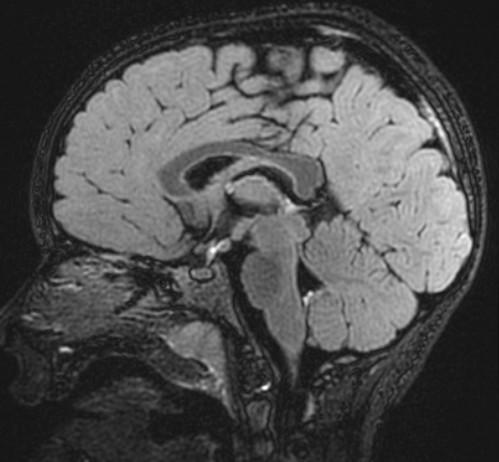

Sag T2 Cube nongated Normal

Normal

Sag T2 Cube

Nongated: CSF dephasing in the aqueduct on this sequence

Primary fissure 3 lobes Closed fastigial point

Sag T2 Cube Normal

Anterior commissure

Corpus Callosum

Rostrum, genu, body, splenium

Sella/Suprasella

ON, post pit bright spot, stalk

Midbrain

Patent aqueduct

Pons

“just right…”

Vermis

3 lobes

Cerebellar Tonsils